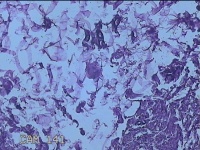

外阴部包块

性别

女

年龄

37岁

临床诊断

皮脂腺囊肿

一般病史

外阴部起包块一月余。

标本名称

大体所见

灰白暗红色包块2.3x1.8x0.8cm一个,表面糜烂,切开包块呈实性,切面灰白淡黄色,质软。

图1

有那么点像脂肪瘤。